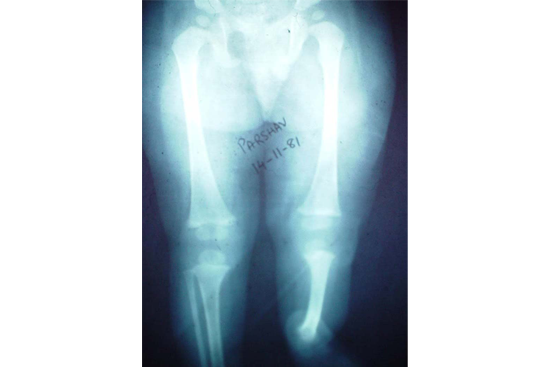

Limb Lengthening